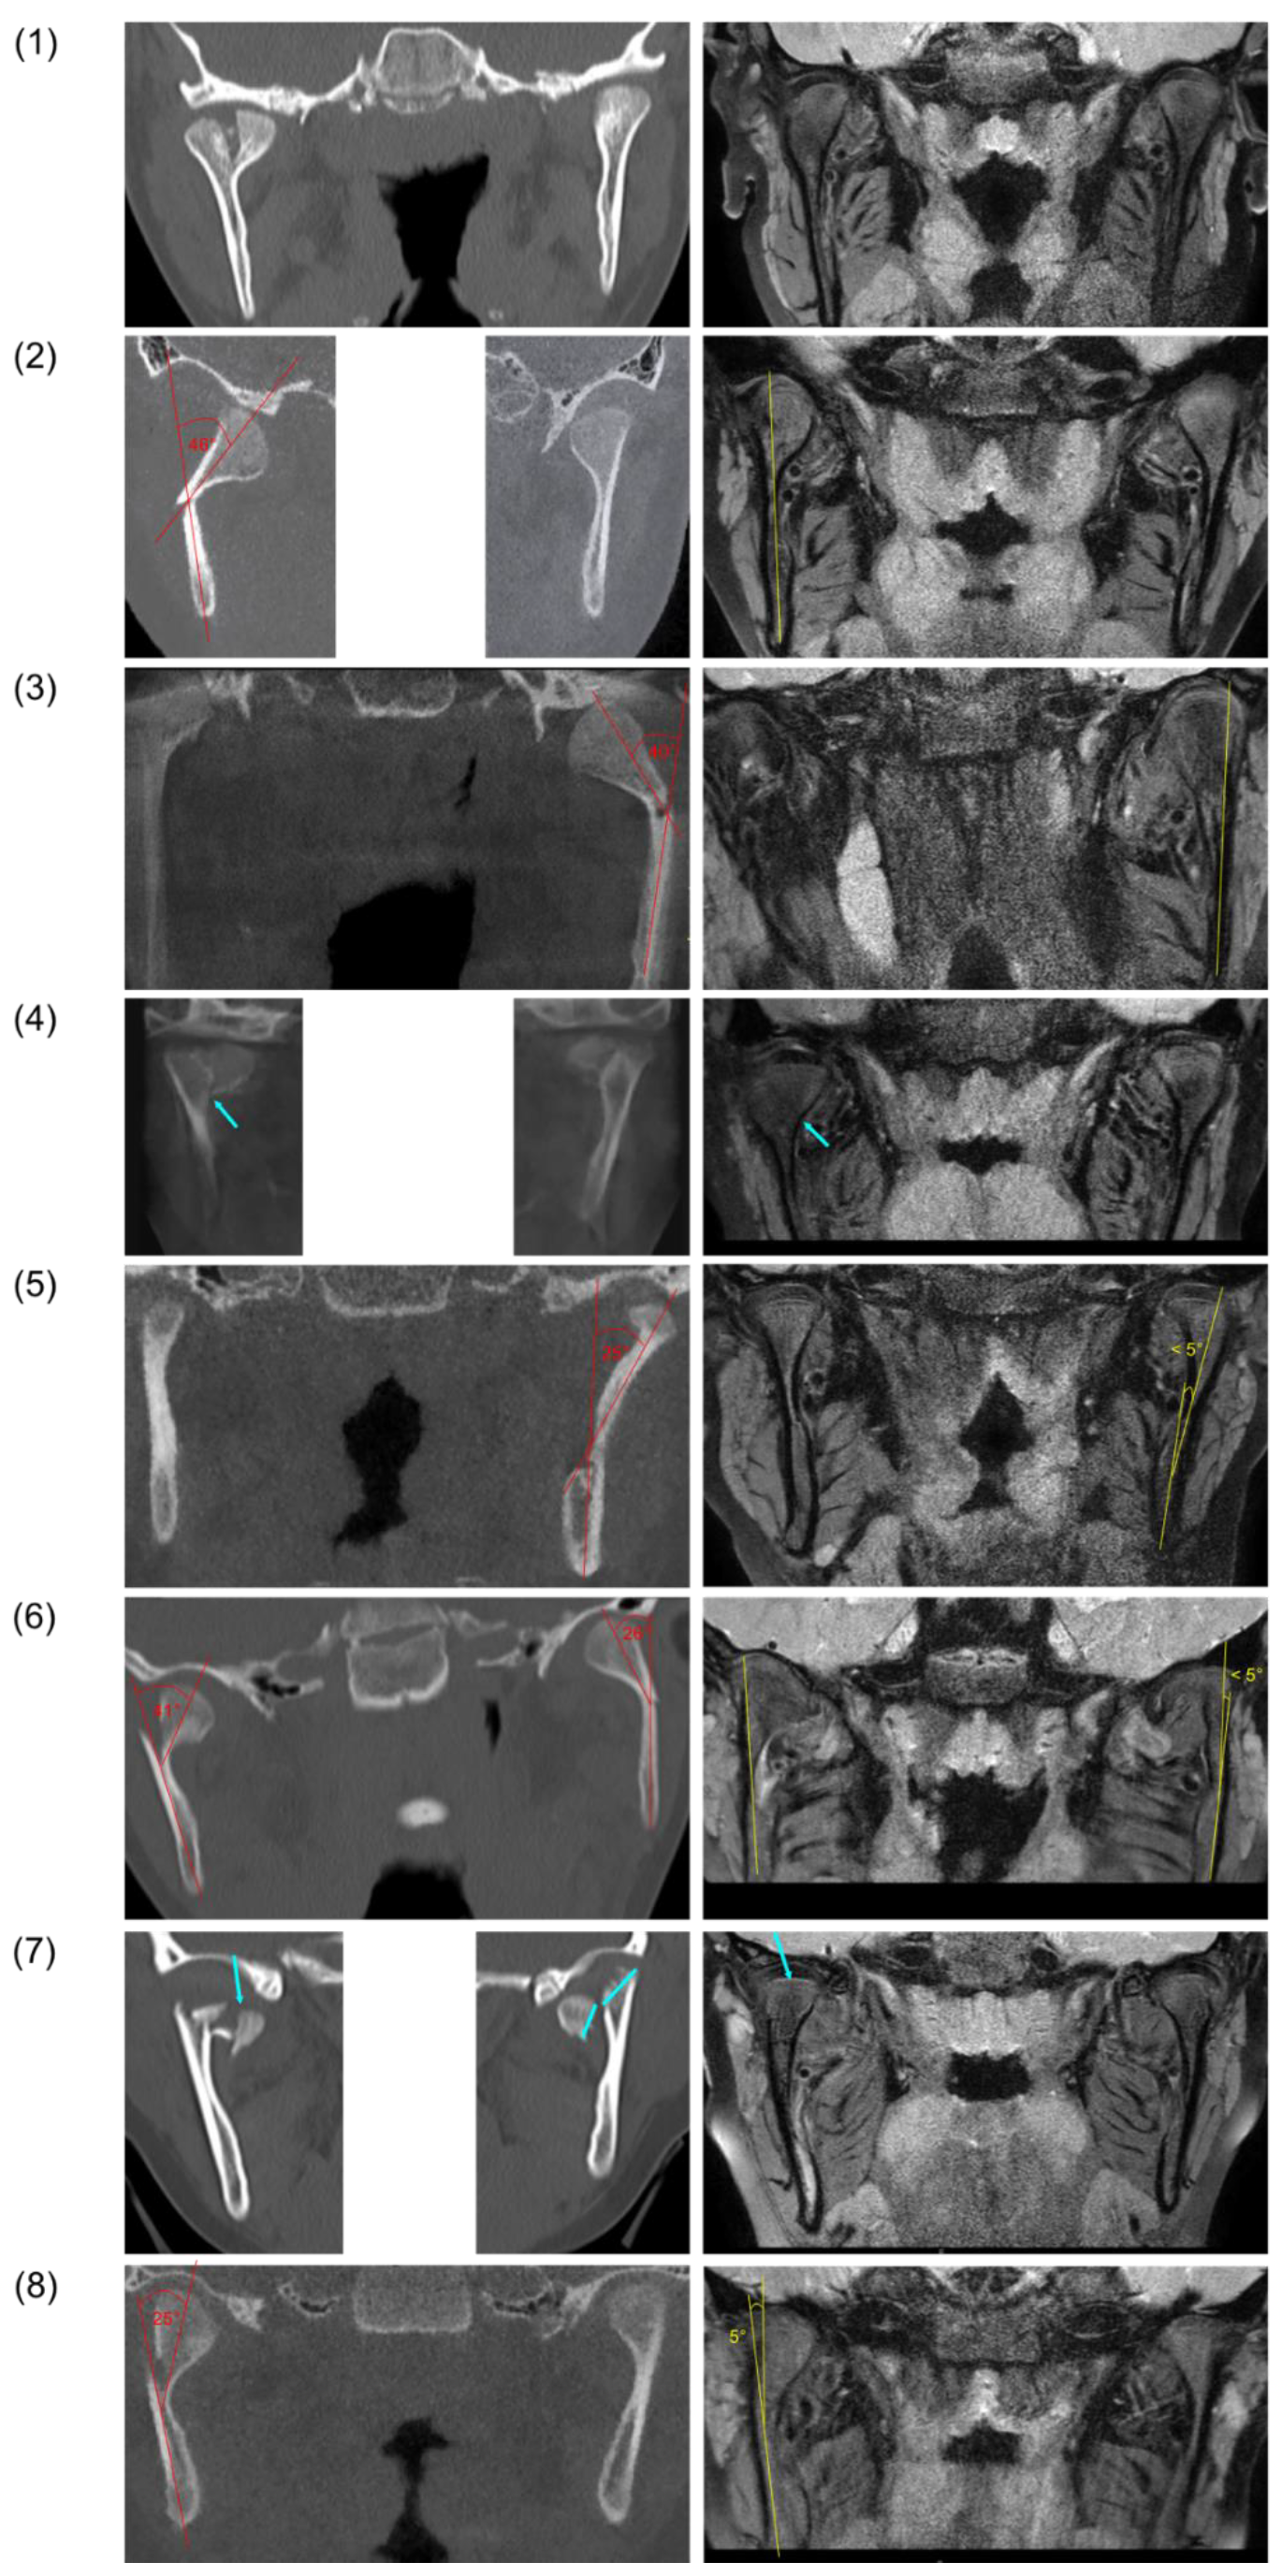

| Case | Sex | Age at Trauma | Type of Trauma/Etiology | Fracture Side | Type of Fracture AO-CMF | Specific Level 3 Condylar Process System Code [30] | ||||||||||

|---|---|---|---|---|---|---|---|---|---|---|---|---|---|---|---|---|

| Location | Fragmentation | Vertical Apposition | Sidewards Displacement | Angulation | Displacement Head Fragment/Fossa | Displacement Caudal Fragment/Fossa | Distortion of Head | Loss of Ramus Height | Angulation in ° | Height Loss in mm | ||||||

| (1) | M | 7 years, 5 months | Bicycle | Right | Condylar head fracture | M | 0 | 0 | - | - | 1, a | - | 0 | 0 | - | 0 mm |

| (2) | M | 5 years, 6 months | Bicycle | Right | Low condylar neck fracture | - | 0 | - | 1 | 2, m | 1, a, m | 0 | 0 | 1 | 46° | 3.2 mm |

| (3) | M | 14 years, 9 months | Fall | Left | Low condylar neck fracture | - | 0 | - | 0 | 1, m | 1, m | 0 | 0 | 1 | 40° | 5 mm |

| (4) | F | 7 years, 3 months | Scooter | Bilateral | Right: condylar head fracture | M | 0 | 0 | - | - | 0 | - | 0 | 0 | - | 0 mm |

| Left: condylar head fracture | M | 1 | 0 | - | - | 0 | - | 0 | 0 | - | 0 mm | |||||

| (5) | M | 10 years, 7 months | Play | Left | Subcondylar fracture | - | 0 | - | 1 | 1, l | 1 | 0 | 0 | 1 | 25° | 4.5 mm |

| (6) | F | 8 years, 10 months | Play | Bilateral | Right: high condylar neck fracture | - | 0 | - | 1 | 1, m | 0 | 0 | 0 | 1 | 41° | 4 mm |

| Left: low condylar neck fracture | - | 0 | - | 0 | 1, m | 0 | 0 | 0 | 1 | 26° | 2 mm | |||||

| (7) | M | 8 years, 6 months | Bicycle | Bilateral | Right: condylar head fracture | P | 1 | 2 | - | - | 1, a | - | 1 | 1 | - | 5.5 mm |

| Left: condylar head fracture | P | 2 | 1 | - | - | 1, a, m | - | 1 | 1 | - | 9 mm | |||||

| (8) | M | 5 years, 7 months | Fall | Right | Subcondylar fracture | - | 0 | - | 1 | 1, m | 0 | 0 | 0 | 1 | 25° | 3 mm |